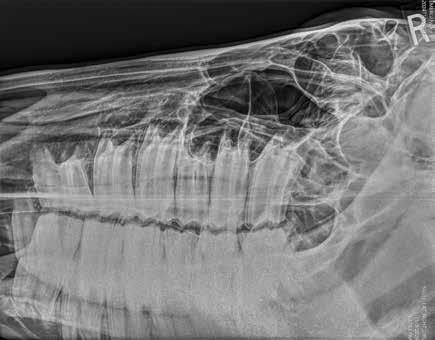

Radiographs are the most common first step in evaluating a horse’s mouth after a thorough exam from a veterinarian. Horses have a complex system of air-filled sinuses in their skull which creates good radiographic images with the contrast of bone and air.

Radiographs can detect diseases in those sinuses as well as changes in teeth arrangement, structure, number, and integrity. Skull radiographs can also be used to find fractures. The complexity of the equine skull makes subtle lesions hard to detect in some cases. It takes a minimum of 4 radiographic views to find problems and oftentimes, it’s still not completely clear what is going on. Additionally, it takes experienced practitioners who routinely interpret skull films to get an accurate diagnosis.

Amir is a horse that received routine extractions of molars and developed nasal discharge. Despite veterinary intervention, he continued to worsen. The radiograph below shows the area of interest as well as the CT images used for diagnosis of the extent of the problem as well as surgical planning. You can see how much more detailed information is available from a CT examination vs plain radiographs. To read and an image from a normal CT scan on the right. more about Amir, find his full case study on our website at https://animalimaging.net/equine-sinusitis/.